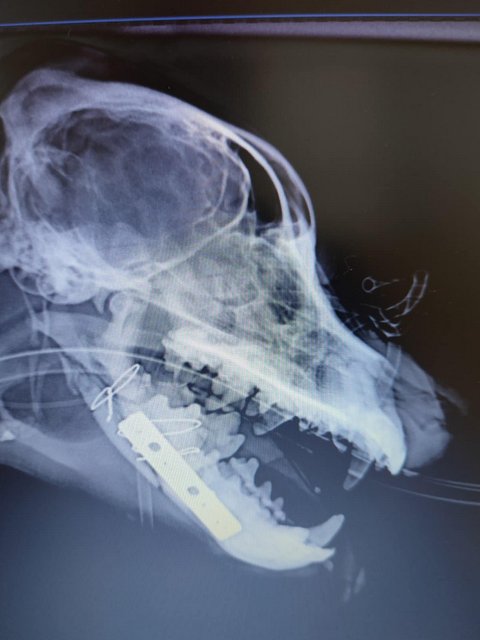

Röntgenbilder zeigten das Ausmaß der Zerstörung des Unterkiefers und den Bruch eines Beines.

Dieser Hund muss grausame Schmerzen haben, Zähne sind aus der Verankerung gerissen und sein Gesichtsschädel ist nicht mehr symmetrisch. Ein großes Stück des Unterkiefers ist komplett abgebrochen.

Camush Kopf ist wieder symmetrisch, der Kiefer wird jetzt mit Platte und Verdrahtung zusammengehalten und ein paar Zähne fehlen jetzt.